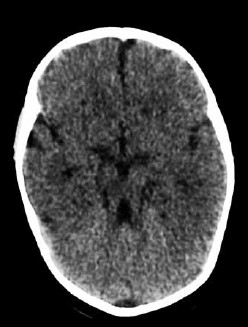

Paciente de dois meses, nascido a termo e com história de anóxia perinatal, realizou a ressonância magnética de crânio mostrada a seguir (imagem ponderada em T1).

As estruturas que comumente são afetadas nessa condição e apresentam hipersinal no exame do paciente são: